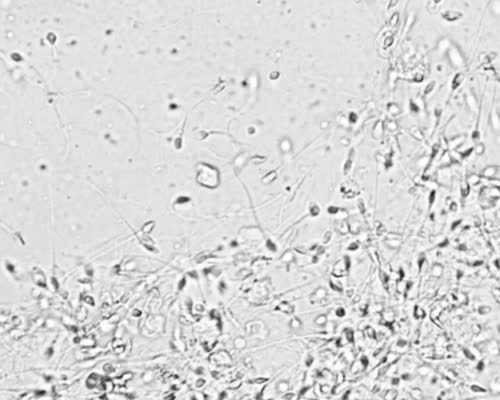

8、无锡妇幼保健院试管婴儿实验室图

10、中国人民解放军第九十二医院生殖医学科创立于1993年,是一家集不孕不育诊断、治疗、科普和科研于一体的现代化综合性医院。该医院拥有大量的专业技术人才和先进设备,包括激光显微手术系统、高端超声诊断仪、精子质量分析仪等,以及多项国际领先的技术和设备。